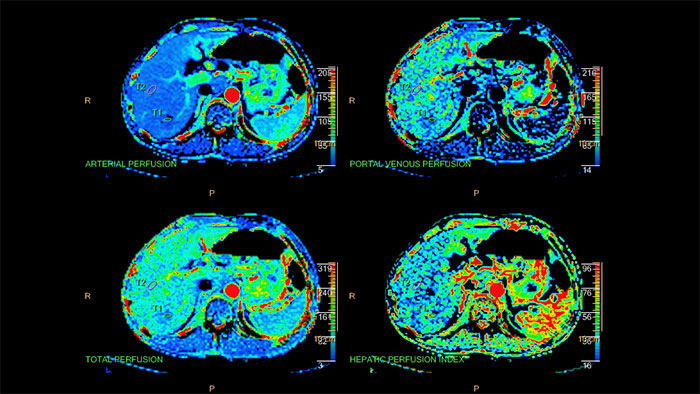

Quantifiable perfusion

CT Body Perfusion is intended for visualization, assessment and quantification of blood flow, blood volume, time to peak and peak enhancement using dynamic CT data. The application provides whole-organ or single-location liver, lung and kidney perfusion calculations.